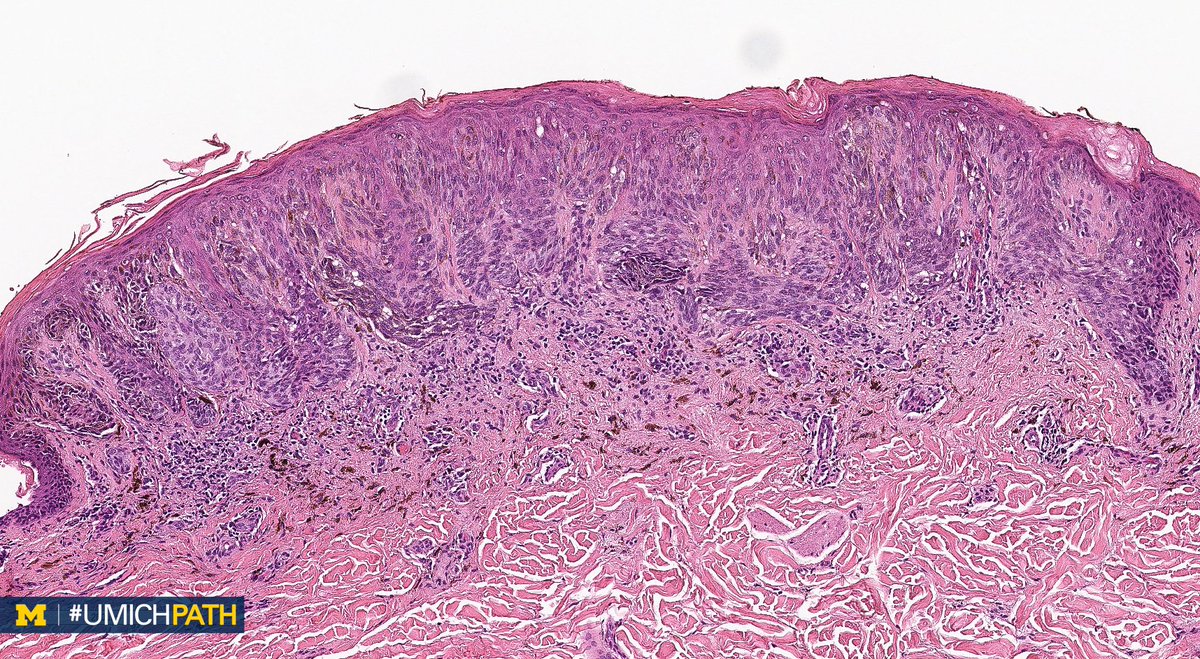

Pigmented spindle cell naevus of Reed pathology image Spindle Cell Nevus Of Reed Spindle cell naevus, epithelioid cell naevus, juvenile melanoma) is a variant of a compound. Pigmented spindle cell naevus of reed appears in children and young adults. pigmented spindle cell nevus is a benign melanocytic lesion that was initially described in 1975 by reed et al. spitz naevus is classified as classic, pigmented, or spindle cell tumour of reed.. Spindle Cell Nevus Of Reed.

Pigmented Spindle Cell Nevus of Reed Dermatopathology Spindle Cell Nevus Of Reed It is generally found on the trunk or. pigmented spindle cell naevus of reed. interestingly, ntrk3 fusion appears to be the most typical genomic aberration in pigmented spindle cell nevus. Pigmented spindle cell naevus of reed appears in children and young adults. Spindle cell naevus, epithelioid cell naevus, juvenile melanoma) is a variant of a compound. pigmented. Spindle Cell Nevus Of Reed.

Pigmented spindle cell naevus of Reed pathology image Spindle Cell Nevus Of Reed pigmented spindle cell nevus is a benign melanocytic lesion that was initially described in 1975 by reed et al. interestingly, ntrk3 fusion appears to be the most typical genomic aberration in pigmented spindle cell nevus. Pigmented spindle cell naevus of reed appears in children and young adults. It is generally found on the trunk or. the spitz. Spindle Cell Nevus Of Reed.

Pigmented spindle cell naevus of Reed pathology image Spindle Cell Nevus Of Reed It is generally found on the trunk or. the spitz naevus (syn. spitz naevus is classified as classic, pigmented, or spindle cell tumour of reed. pigmented spindle cell nevus (pscn), also known as reed nevus, is a distinctive melanocytic tumor that can show. Spindle cell naevus, epithelioid cell naevus, juvenile melanoma) is a variant of a compound.. Spindle Cell Nevus Of Reed.